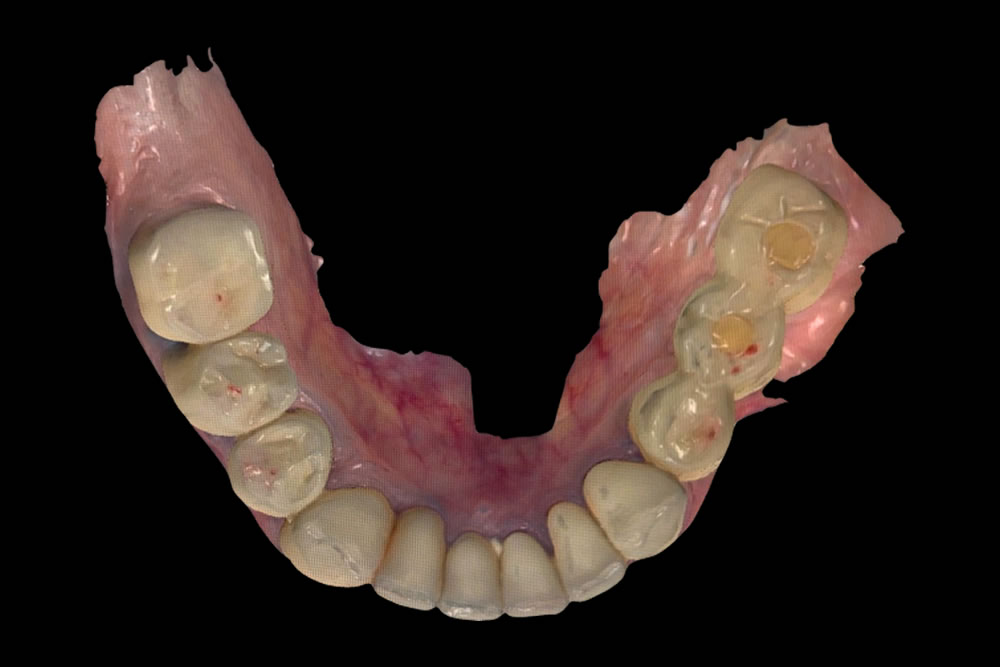

セラミックへの置き換え

治療終了時の口腔内

下顎はインプラントおよびセラミックによる補綴治療を行い、上顎は保険適用の義歯を装着しています。

術前と比較して咬み合わせが安定しました。歯の傾斜も改善され、審美的にも患者さまにご満足いただけました。下顎は補綴前に必要部位の根管治療を行っています。X線写真上、下顎右4番の根尖病変は縮小傾向を示しています。